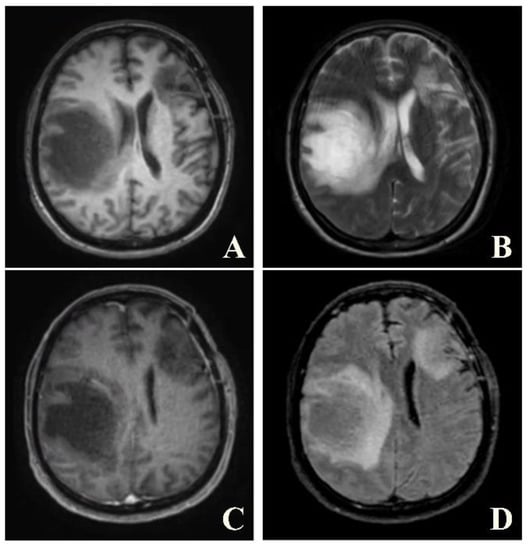

Figure 2.

Axial T1W (A), T2W (B), post-contrast T1W (C) and post-contrast FLAIR (D) images of the same patient reveal tumor-like lesion with surrounding vasogenic edema at left frontal and right parietal lobes. The patient was suspected to have high-grade glioma and underwent biopsy. Pathological result was consisted with demyelination, yielding a final diagnosis of tumefactive MS. The patient was given treatment with high-dose steroids.

Figure 3.

A follow-up axial post-contrast FLAIR image of the same patient performed one year after the diagnosis, showing marked improvement in lesions.